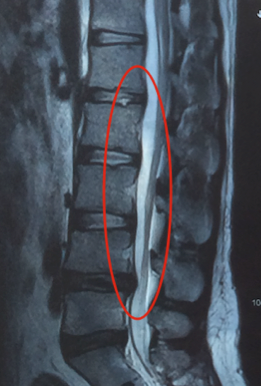

A protrusão de disco vertebral, por sua vez, consiste na deformação do anel fibroso do disco intervertebral, sem saída do conteúdo (Fig. 3).

Fig. 3